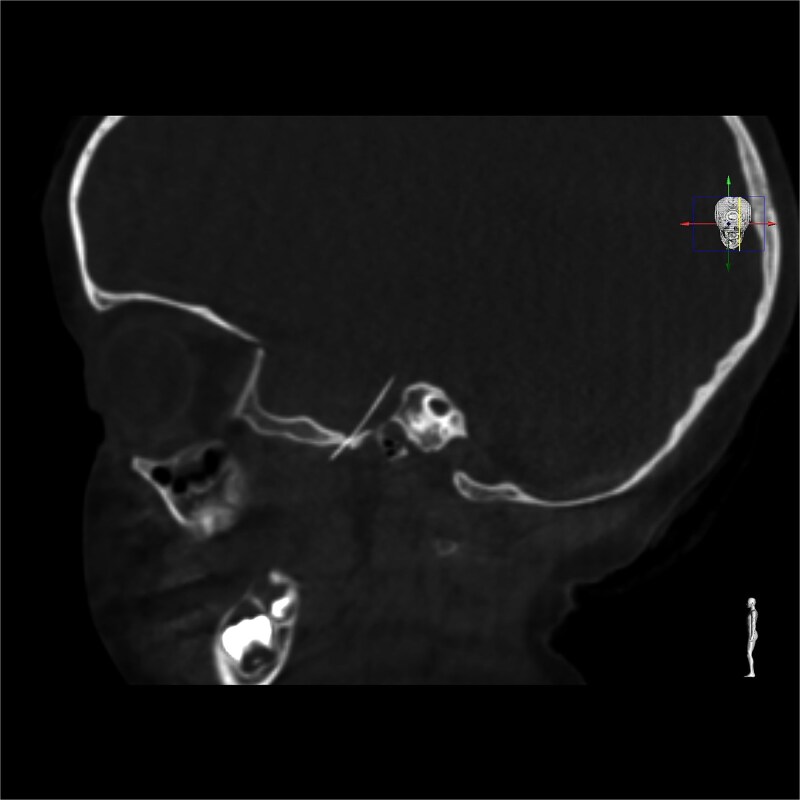

局部麻醉和神经阻滞是牙科治疗中常用的方法。虽然它们的并发症发生率较低,但局部事件如针头骨折可能导致危及生命的后果。我们提出一个病例针头骨折在一个4岁的女孩谁接受了一个小牙科手术。针通过卵圆孔向颅内移动。她需要一个多学科的管理和最后的神经外科干预,以去除它。除了初步诊断计算机断层扫描(CT)外,最重要的是获得术中成像工具(儿科人群最好是低辐射CT)来监测针移的潜在风险。该报告表明,除其他并发症外,断针可能向颅内移位,强调了在拥有适当设备和专家的三级转诊医院处理这些病例的重要性。

Local anaesthesia and nerve block are common practices in dental therapy. Although they are associated with low rate of complications, local events such as needle fracture could entail life threatening consequences. We present a case of a needle fracture in a 4 year old girl who underwent a minor dental procedure. The needle migrated intracranially through the foramen ovale. She required a multidisciplinary management with a final neurosurgical intervention in order to remove it. In addition to an initial diagnostic computerized tomography (CT), it was of utmost importance to have access to an intraoperative imaging tools (preferably low radiation CT in paediatric population) to monitor the potential risk of needle migration. This report demonstrates that a broken needle may migrate intracranially, among other complications, underscoring the importance of managing these cases in a tertiary referral hospital with the appropriate equipment and specialists.